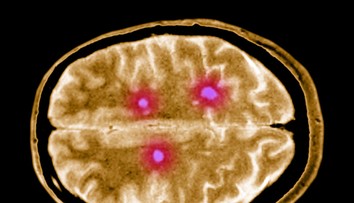

Danielin život však nie je len ružový ako jej kresby. Začiatkom tohto roka jej lekári potvrdili vážnu diagnózu. „Skleróza multiplex mi zasiahla do života od januára tohto roku,“ hovorí.

„V januári som začala vidieť cez ľavé oko čierny pás. Bola som aj vyčerpaná a unavená, ale vtedy som mala dieťa mladšie ako rok, takže to bolo úplne normálne. Očný mi prvý raz povedal, že by tam mohla byť skleróza. Mala som zápal zrakového nervu,“ spomína.